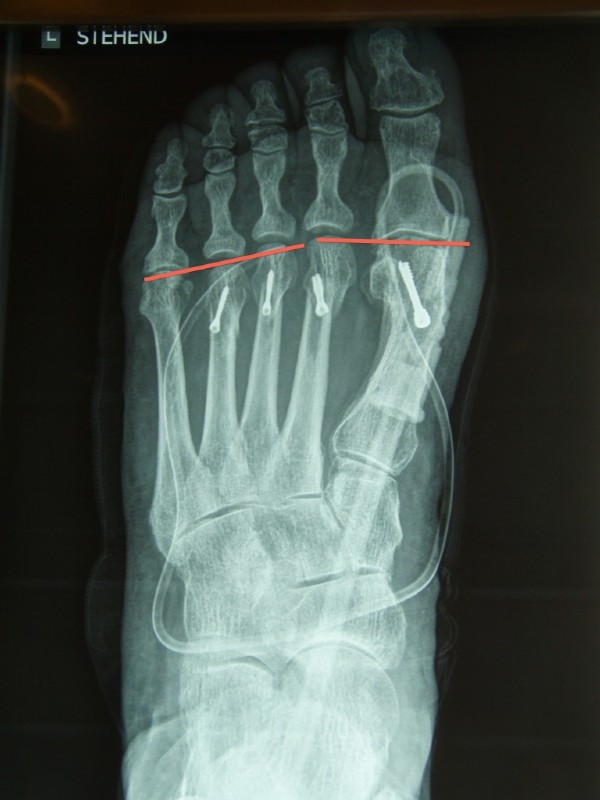

Eingezeichneter "Mittelfußindex" (oder Parabel oder Alignment)

Links: Die Mittelfußknochen II und III und IV sind zu lang und bilden nicht die notwendige Parabel, die Folge sind Überlastungen, Schmerzen und Schwielen im Ballenbereich.

Rechts: So soll es sein: Nach der Operation ist der 1. Strahl (Mittelfußknochen) der Längste, der 2. ist etwa gleich lang oder etwas kürzer, der 3. wieder etwas kürzer, usw.

Die roten Striche zeigen die geplanten Verkürzungen bei der Reparaturoperation.

An beiden Füßen mussten Verkürzungen der Mittelfußknochen gemacht werden. Die Parabel wurde erreicht, und die Spreizfußschmerzen verschwanden nach kurzer Zeit.